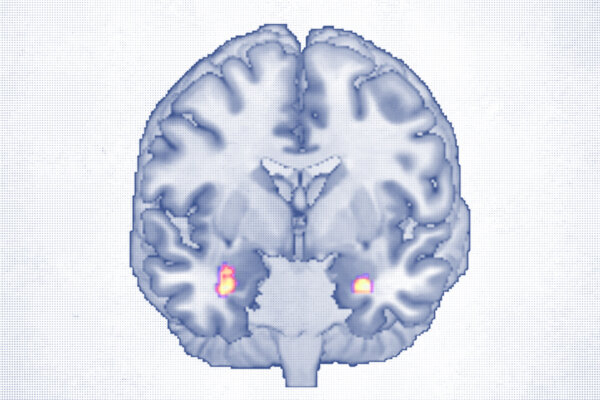

Cognitive Behavioral Therapy Reshapes Brain Structure

First-ever brain scans show how therapy grows brain matter in regions linked to mood regulation.